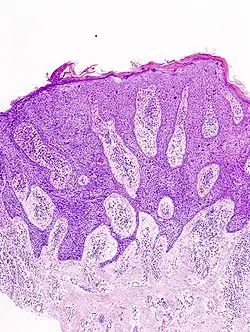

In situ disease

Bowen's disease is essentially equivalent to and used interchangeably with cSCC in situ, when not having invaded through the basement membrane.[12] Depending on source, it is classified as precancerous[13] or cSCC in situ (technically cancerous but non-invasive).[48][49] In cSCC in situ (Bowen's disease), atypical squamous cells proliferate through the whole thickness of the epidermis.[12] The entire tumor is confined to the epidermis and does not invade into the dermis.[12] The cells are often highly atypical under the microscope, and may look more unusual than the cells of some invasive squamous-cell carcinomas.[12]

cSCC in situ, high magnification, demonstrating an intact basement membrane.[12] -

cSCC in situ -

cSCC in situ